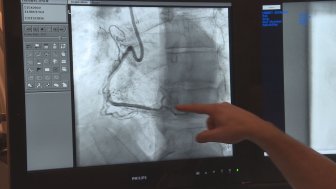

MUHC’s Got Talent competition raises $677, 000 for research and cutting edge technologyMontreal doctors are revealing their hidden talents in a friendly talent competition organized by the MUHC foundation, to raise funds for different causes close to their hearts.CanadaNov 17, 2022